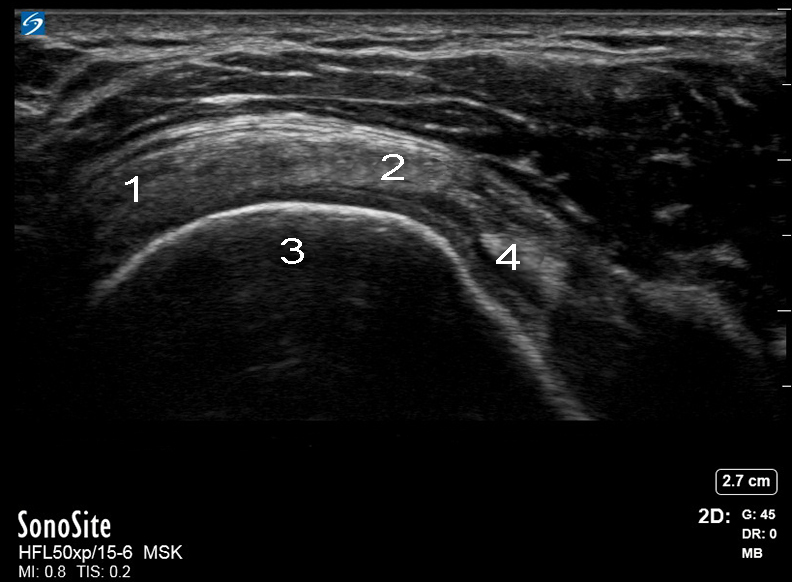

Bild: Schulter, Rotatorenmanschette, transversale Achse

1. Infraspinatus

2. Supraspinatus

3. Humeruskopf

4. Bizepssehne